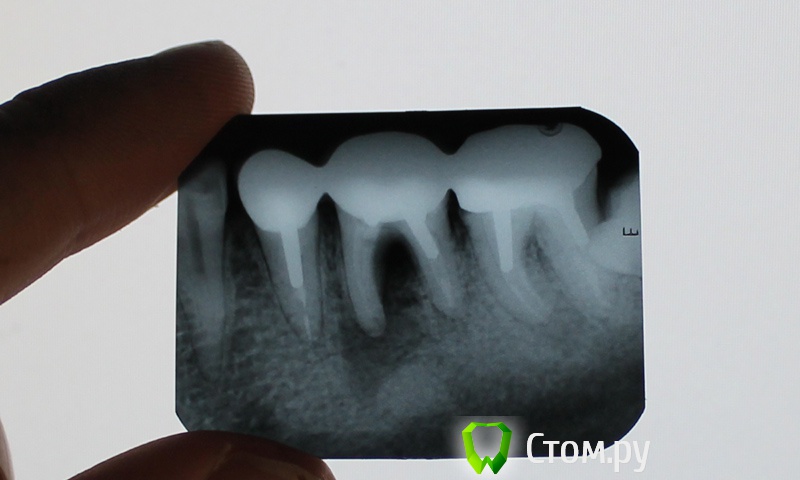

Алексей-Спб Опубликовано 11 марта, 2014 Поделиться Опубликовано 11 марта, 2014 Здравствуйте, извините если не в тот раздел пишу, но вроде как проблема связана с протезированием...Всегда лечился в государственной стоматологической поликлинике, но 3 года назад в январе 2011 года мне сказали, что надо менять все боковые зубы и я решил обратиться в частную клинику, всё-таки ответственный момент. Там мне заменили все 12 боковых зубов, сверху и снизу, поставили металлокерамику. Конечно обошлось дорого, но нареканий никаких не было, 3 года ничего не беспокоило. В ноябре прошлого года, разболелся зуб (вроде бы нижняя правая 6-ка), он у меня под коронкой. Сходил в ту же клинику где ставил металлокерамику. Ничего не нашли, рентген сказали нормальный, вмешательство не требуется, а проблема видимо в том, что мол я застудил зуб (ну в принципе это было похоже на правду) выписали лекарств, полоскание содой, и в течении 5 дней всё прошло. Ну я успокоился.Сейчас зуб меня не беспокоит, но в прошлую пятницу распухла десна, не больно, но мало ли что. Позвонил в ту же клинику, но там деснами не занимаются. Так что сегодня съездил в общегородскую. Врач посмотрела и сказала, что 6-ке моей кранты, сказала что там киста, и всё совсем ужасно и чуть ли не гниение кости и сказала чтобы я срочно бежал к протезисту снимал всю металокерамику, и удалял зуб.Я рассказал, что в клинике где мне ставили керамику 4 месяца назад ничего не нашли и сказали что всё в порядке, но врач говорит, что там настолько всё ужасно, что не заметить они не могли, и вообще не разбираются и зуб сохранить и вылечить невозможно. Теперь у меня дилемма. Родители предлагают снова идти в ту же частную клинику, мол сами делали пусть и снимают, да и качественней там и они там профессионалы не могут ошибаться.А я вот теперь сомневаюсь в их профессионализме, ведь как мне сегодня сказали, это невероятно что они могли не заметить, что зуб почти на грани и я подумываю чтобы действительно поехать в бесплатную клинику и удалить зуб, хотя и очень жалко, он ведь даже не болит у меня. Хотелось бы узнать мнение специалистов, стоит ли идти в дорогую клинику где делали протезирование, но не заметили болезни или действительно поехать завтра в бесплатную и там удалить?И ещё есть какой-нибудь шанс спасти зуб, может там залечить болячку и новую керамику поставить? или теперь только единственный выход удаление? Ссылка на комментарий